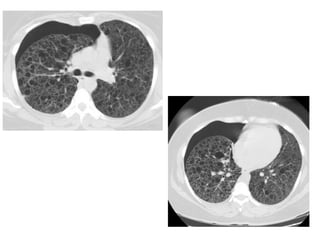

(a) UIP is characterized by heterogeneous lung abnormalities consisting of

subpleural honeycombing (arrowhead), reticular opacities, and traction

bronchiectasis, (b) NSIP demonstrates homogeneous lung involvement with

predominance of ground-glass opacity combined with sub-pleural linear

opacities and micronodules. The microcysts in NSIP (arrowhead) are much

smaller than the honeycombing in UIP